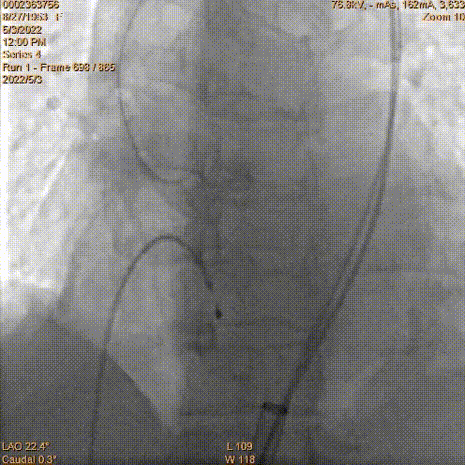

工作位冠脉球扩

瓣膜释放2/3同时发现患者血压降低,立即释放冠脉支架